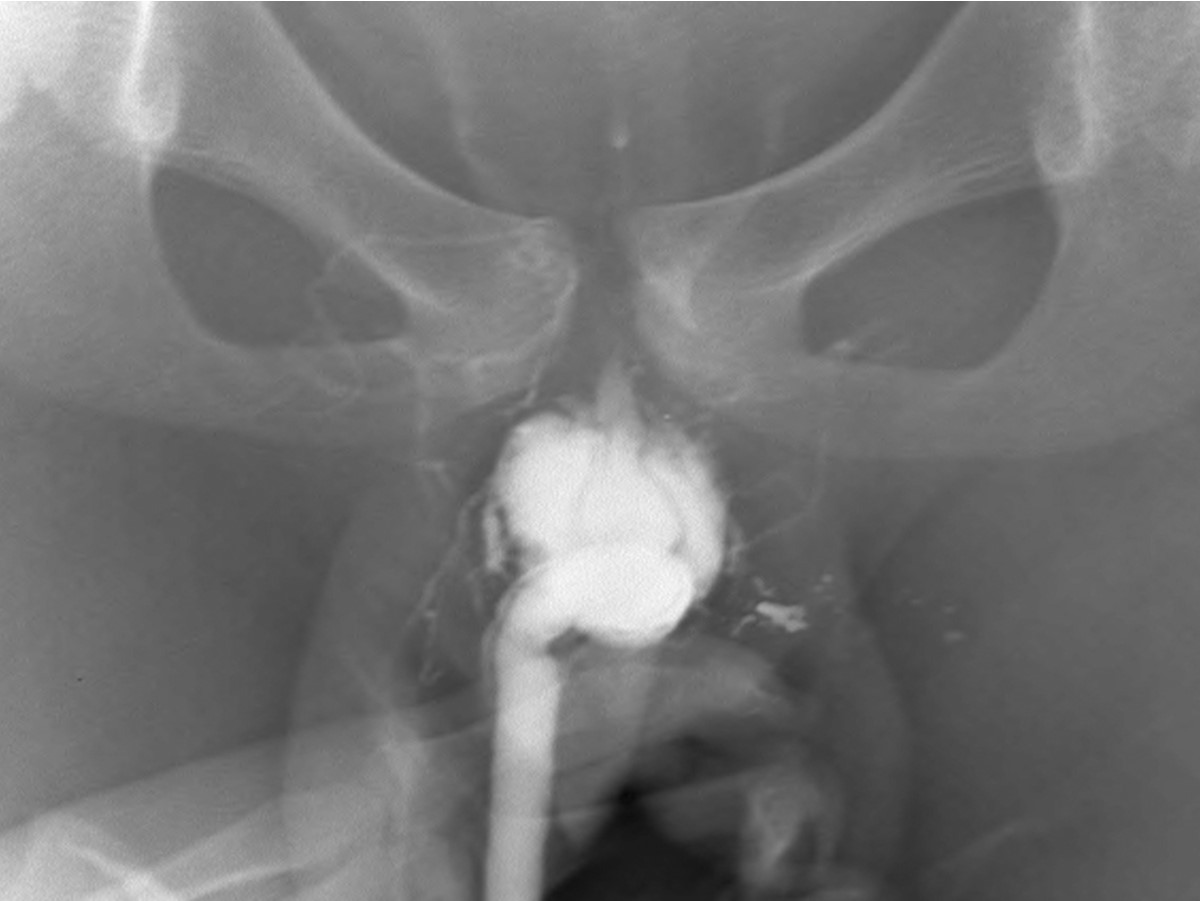

역행성 요로 조영술(Retrograde urethrogram)에서 조영제가 구부요도(bulbous urethra)주위로 새어나가는 소견이 보였다(Fig, 1).

Fig. 1.

Fig. 1. Retrograde urethrogram after trauma shows a large amount of contrast material extravasation around bulbous urethra without flow into the prostatic urethra or bladder.